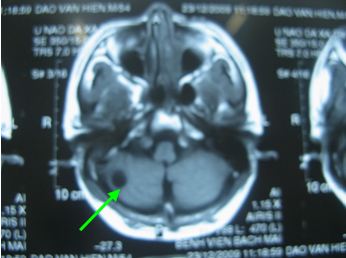

Chụp cộng hưởng từ sọ não

Kết quả: xuất hiện 1 khối tổn thương dạng thứ phát vùng bán cầu tiểu não phải kích thước 32x33mm, phù não quanh khối.

Chụp MRI sọ não

Trước điều trị: Xuất hiện 1 khối tổn thương dạng thứ phát vùng bán cầu tiểu não phải, kích thước 32x33mm, phù não quanh khối

Sau điều trị: Khối tổn thương dạng kén dịch vùng bán cầu tiểu não phải, kích thước thu nhỏ còn 14x12mm, không có phù não xung quanh